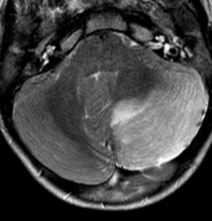

МРТ головного мозга. Т2-взвешенная аксиальная МРТ. Постинфекционный церебеллит.

Постинфекционные неврологические нарушения возникают по типу аутоиммунных реакций. Обычно они объединяются в единый термин ” острый диссеминирующий энцефаломиелит” (ОДЭМ), который течет доброкачественно в разных вариантах. ОДЭМ протекает в форме демиелинизации, что отчетливо видно при МРТ головного мозга. В отличие от рассеянного склероза очаги имеют отчетливую динамику с постепенным их исчезновением на Т2-взвешенных МРТ головного мозга. К более редким вариантам относится церебеллит, когда на МРТ головного мозга виден участок отека мозжечка, часто компрессия 4 желудочка с проводниковой гидроцефалией. Неврит зрительного нерва может рассматриваться как демиелинизация при ОДЭМ или дебют рассеянного склероза (например, при оптикомиелите Дэвика). Течение по типу полирадикулопатии относится к синдрому Гийена-Барре. Соответственно при МРТ с контрастированием при синдроме Гийена-Барре наблюдается усиление пораженного лицевого нерва или при МРТ позвоночника - корешка спинного мозга, а иногда и всего конского хвоста.